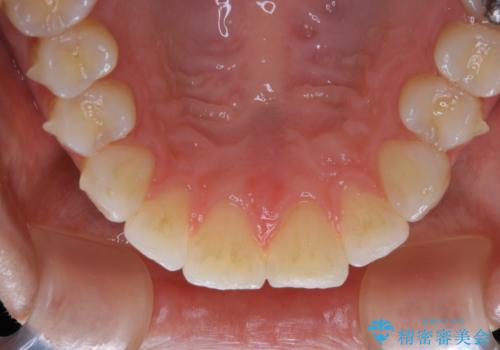

- インビザライン矯正治療中にステインが気になるとのことで来院されました。全体的にステインが付着していたため自費クリーニングPMTC(60分コース)を行いました。

インビザライン矯正治療中は、ご自身の歯にアタッチメントという突起物(効率的に歯の移動を行うため)をつけます。そのため、通常時よりもステインが付きやすい状態になることがあります。

インビザラインは透明なマウスピースなので、ご自身の歯にステインなどが付着していると、見た目に影響してしまうことがあります。

矯正治療中の虫歯・歯周病・口臭予防としても、定期的にPMTCを行うことが大切です。